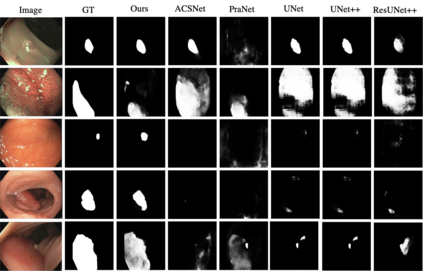

Polyp segmentation is of great importance in the early diagnosis and treatment of colorectal cancer. Since polyps vary in their shape, size, color, and texture, accurate polyp segmentation is very challenging. One promising way to mitigate the diversity of polyps is to model the contextual relation for each pixel such as using attention mechanism. However, previous methods only focus on learning the dependencies between the position within an individual image and ignore the contextual relation across different images. In this paper, we propose Duplex Contextual Relation Network (DCRNet) to capture both within-image and cross-image contextual relations. Specifically, we first design Interior Contextual-Relation Module to estimate the similarity between each position and all the positions within the same image. Then Exterior Contextual-Relation Module is incorporated to estimate the similarity between each position and the positions across different images. Based on the above two types of similarity, the feature at one position can be further enhanced by the contextual region embedding within and across images. To store the characteristic region embedding from all the images, a memory bank is designed and operates as a queue. Therefore, the proposed method can relate similar features even though they come from different images. We evaluate the proposed method on the EndoScene, Kvasir-SEG and the recently released large-scale PICCOLO dataset. Experimental results show that the proposed DCRNet outperforms the state-of-the-art methods in terms of the widely-used evaluation metrics.